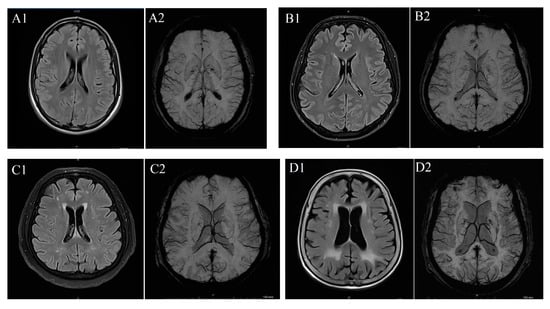

To determine WMH severity, the Fazekas scale was applied to FLAIR MRI data in the axial plane, following standard guidelines [11]. According to this scale, WMH was scored in categories between 0 and 3: “0” meaning absence of WMH; “1” meaning dotted WMH; “2” meaning early combined WMH; and “3” meaning WMH in large combined areas (Figure 1) [15]. The scale was selected due to its widespread clinical use, reproducibility, and suitability for retrospective MRI-based evaluation of WMHs.

Figure 1.

(A) T2 FLAIR (A1) and SW (A2) imaging in a patient with Fazekas 0 case, (B) T2 FLAIR (B1) and SW (B2) imaging in a patient with Fazekas 1 case, (C) T2 FLAIR (C1) and SW (C2) imaging iin a patient with Fazekas 2 case and (D) T2 FLAIR (D1) and SW (D2) imaging in a patient with Fazekas 3 case.